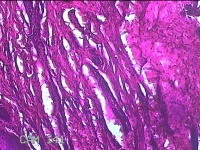

性别

女

年龄

61岁

临床诊断

鸡眼

一般病史

发现左足结节,伴局部疼痛不适2年余。

标本名称

左足结节

大体所见

灰白暗红色带皮肤样结节2.3x1.2x0.3cm一个,表面糜烂,切开结节呈实性,切面灰白暗红色,质硬。